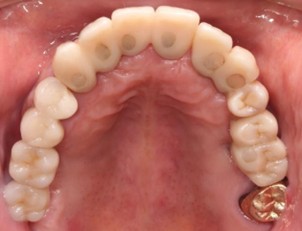

20代 男性

治療前

治療後

治療後- リスク・副作用

- 術後疼痛、歯肉腫脹

- 治療の費用

- 合計¥701,000(税込)

【内訳】

インプラント(1本)¥440,000

その他費用¥261,000

(薬・注射・レントゲン・CT・データ分析・骨造成・サージカルステント・血液検査・仮歯) - 年齢/性別

- 20代/男性

- 患者の具体的な症状

- 1年前に左上12 右上1の根の治療をし、その後放置していたら、左上2が破折した。

左上2インプラント補綴 左上1右上1オールセラミック装着。

歯根破折と虫歯による痛み、審美障害を主訴として来院。 - 検査方法

- コーンビームCT、レントゲン撮影

- 診断結果

- 左上2 歯根破折

- 治療詳細

- 左上抜歯後、インプラント埋入1本

骨造成あり 局所麻酔

インプラント治療後、左上1右上1セラミック修復2本 - 通院回数

- 9回

- 治療期間

- 12か月